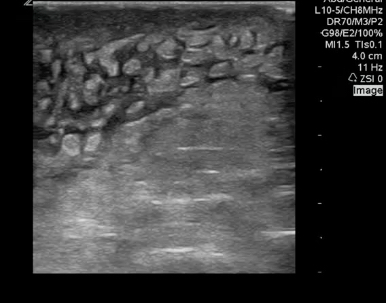

CEllulitis - CobbleStoning